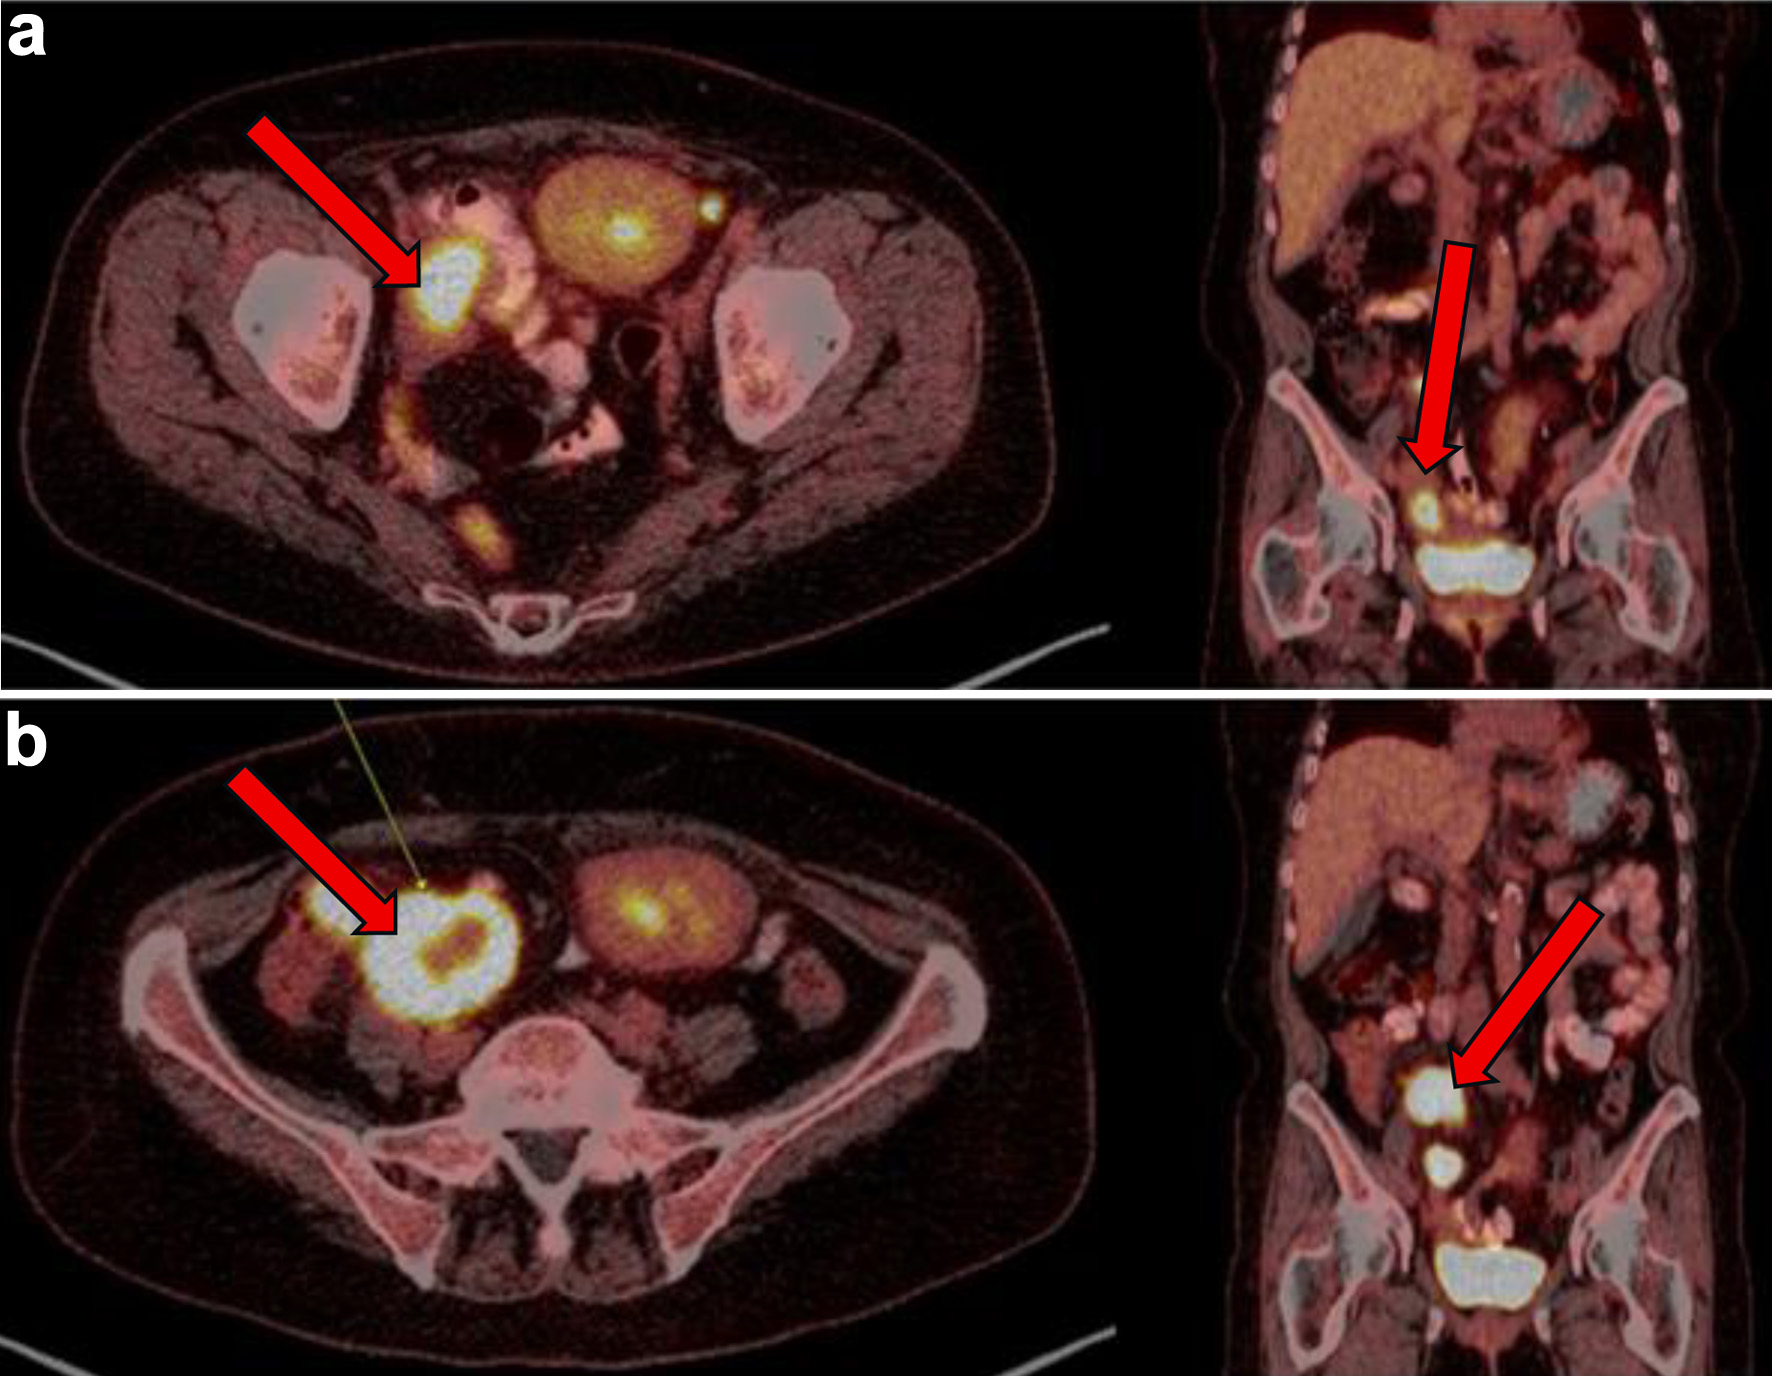

Following six cycles of R-CHOP however, 4 months after her EBV-negative DLBCL diagnosis, the patient’s disease was noted to have progressed. New lesions were identified on a follow-up PET scan, including right pelvic lymph nodes, ileal thickening, and ascending colon lesions, which were concerning for intestinal involvement (Fig. 3). She subsequently had a biopsy of this right pelvic lymph node which showed focal residual DLBCL, germinal center type with extensive necrosis. Biopsy showed that large atypical lymphoid cells are positive for BCL6, CD10, CD20, CD79a, PAX5, and Ki-67 (over 90%) stains.

Figure 3. (a) PET showing metabolic activity of right sided pelvic lymph nodes/nodal masses (arrows) at 3 months from initial presentation. (b) PET conducted 4 months after initial presentation with diffuse terminal ileum/ascending colon thickened wall uptake and increase in size and metabolic activity of right-sided pelvic lymph nodes/nodal masses (arrows), consistent with persistent lymphoma. PET: positron emission tomography.